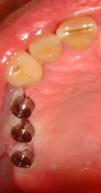

Au terme de cette période, la gencive est de nouveau incisée pour exposer la tête de l’implant et poser une vis de cicatrisation qui guidera la cicatrisation gingivale avant la réalisation de la couronne sur l’implant par le dentiste.

Photo vis de cicatrisation